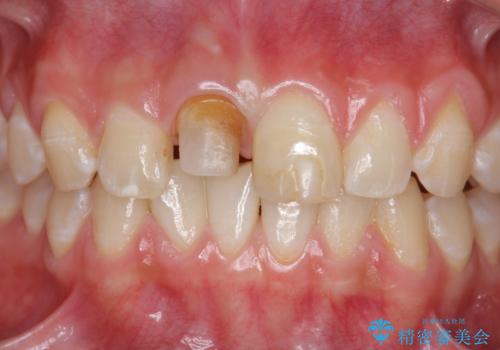

前歯をきれいにしたい ジルコニアクラウンによる審美治療

- 前歯の見た目の改善を求めて来院されました。

ジルコニアクラウンによる審美性の改善を計画します。

失活歯のため捻転を改善し、根管治療は特に希望されなかったのでそのままとしました。

- 11万円(仮歯・ジルコニアクラウン)費用は治療当時の料金となります

今回失活歯であったため捻転を取り反対側の前歯に揃えて補綴を行うことができました。